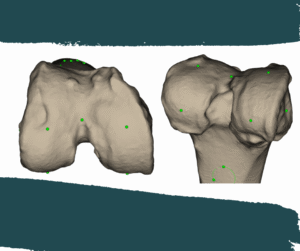

Using the scan data, a highly accurate 3D digital model of your knee is created. This model becomes the foundation for your personalised surgical plan.

With advanced software, Dr Hockings reviews your alignment, joint wear, and bone thickness. He applies kinematic alignment principles to design a surgical plan that matches your natural knee movement.

Manufacturing of PSI guides

The finalised plan is sent to a specialist manufacturing facility in Switzerland, where your 3D-printed patient-specific cutting guides are created and sterilised before your procedure.